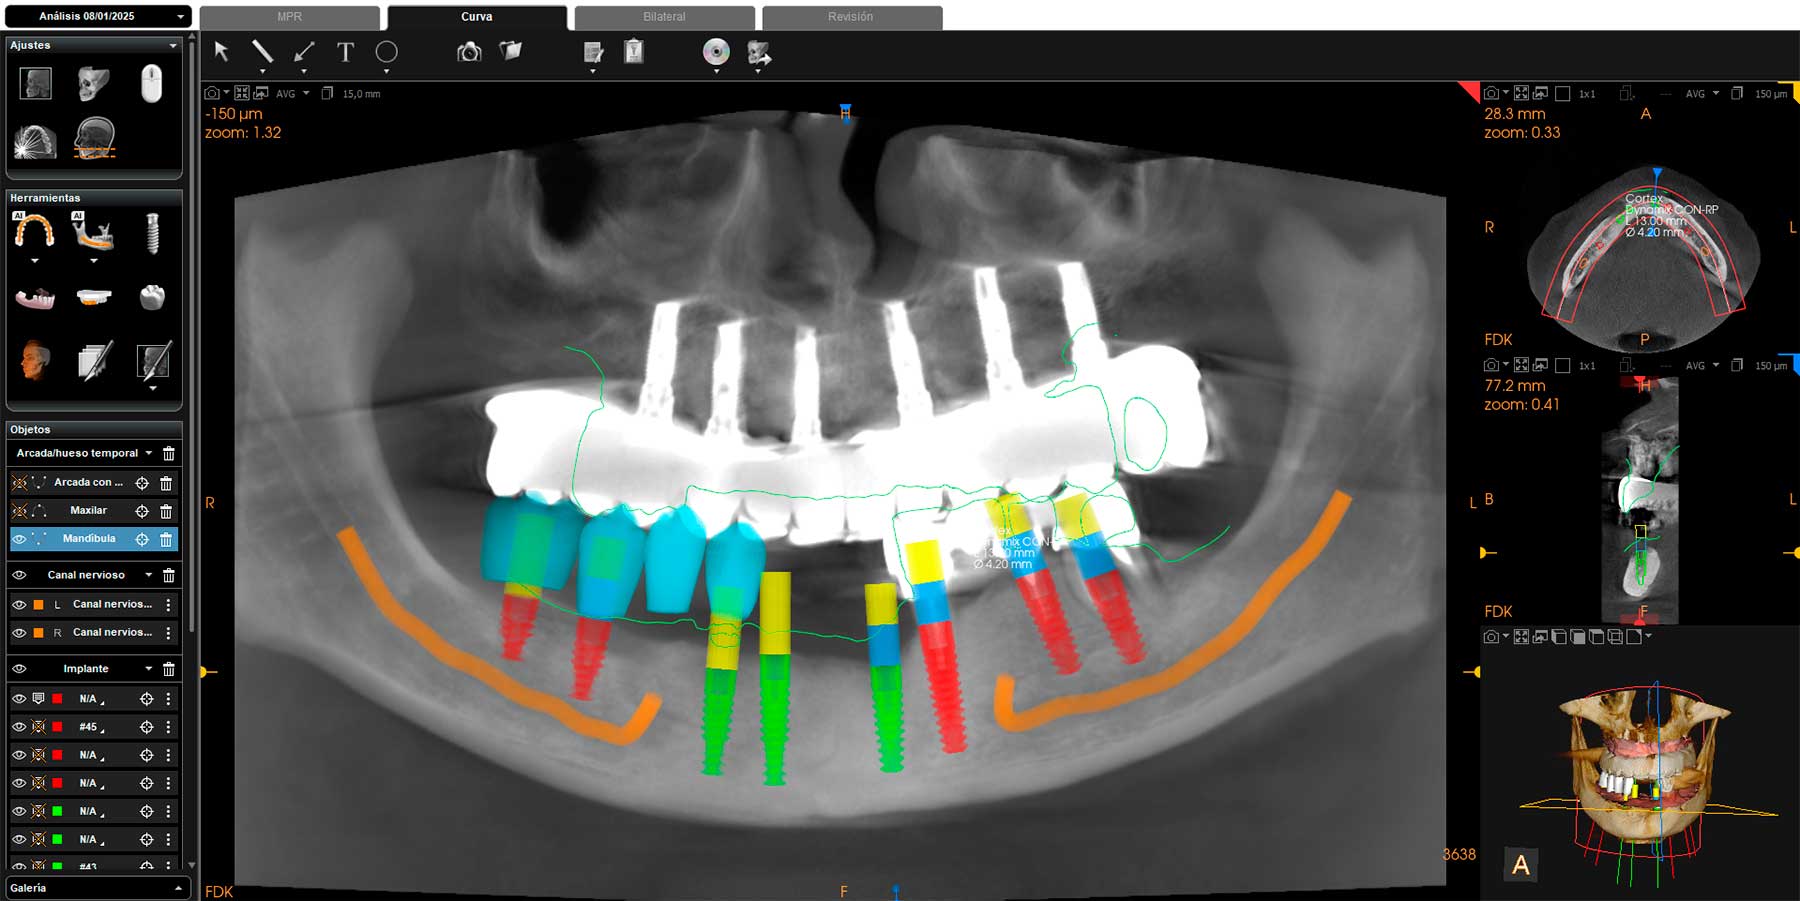

Férulas Guiadas para Implantes

Combinando la Tomografía Computarizada de haz Cónico (CBCT), la informática y el diseño virtual 3D, podemos colocar los implantes de manera totalmente precisa y previsible, mediante guías quirúrgicas de impresión 3D realizadas en el propio centro.

En determinados casos podemos colocar “Dientes en un día”, donde realizamos la extracción de los dientes dañados, la colocación de los implantes y las prótesis en una sola visita, gracias a que aplicamos tecnología de resonancia magnética intraoral para determinar la estabilidad primaria de los implantes que acabamos de colocar.